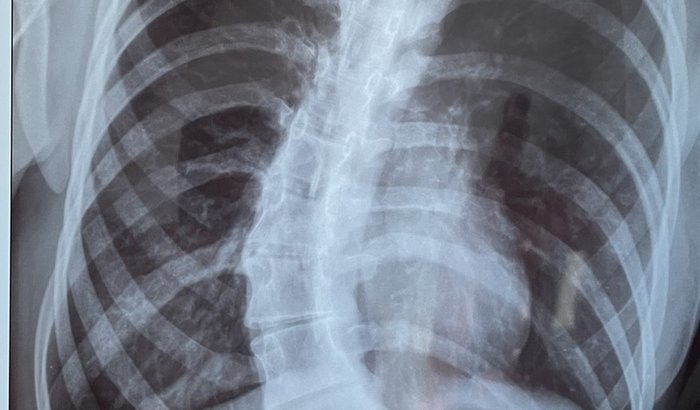

Oii, meu nome é Gabrielly Rodrigues e PRECISO DA SUA AJUDA! Tenho 18 anos e por mais de 10 anos convivo com escoliose, uma condição médica em que a coluna vertebral apresenta uma deformação lateral em forma de curva. De acordo com os últimos exames que fiz em outubro de 2021 minha coluna estava com uma curvatura de 52° (quantidade de graus que SOMENTE CIRURGIA poderá resolver) e com o tempo ela vai se desenvolvendo cada vez mais e prejudicando alguns órgãos. Minha jornada com o SUS é desgastante e até hoje não obtive resposta. E para ser realizada em hospitais particulares, seu custo é de aproximadamente 75 mil reais (orçamento realizado também em outubro de 2021). Porém, preciso realizar essa cirurgia com máxima urgência, pois além do incômodo e sentir bastante dores, está afetando meu desenvolvimento pessoal e de meus orgãos. Mas infelizmente não possuo condições para realizá-la. Dessa forma, venho pedir ajuda de quem realmente pode me ajudar, seja de qualquer maneira ou valor. Pois os meios que possuo são limitados e acredito que com a ajuda de vocês eu posso realizar essa tão sonhada cirurgia.